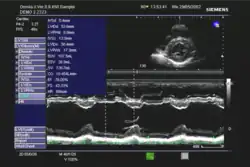

Die Ejektionsfraktion kann mit verschiedenen Untersuchungsverfahren gemessen werden, in absteigender Häufigkeit:

- Echokardiographie

In der klinischen Praxis erfolgt die Abschätzung der Ejektionsfraktion häufig nach dem visuellen Eindruck; dies wird bei subjektiv normaler Pumpfunktion als ausreichend angesehen. Bei eingeschränkter Pumpfunktion sollte eine quantitative Bestimmung mit Hilfe der Scheibchensummationsmethode nach Simpson erfolgen;[3] die Quantifizierung mittels M-Mode nach Teichholz wird als zu ungenau angesehen.[3][4]